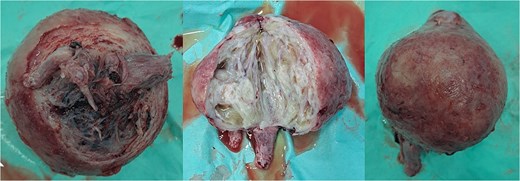

Within the operation, a urinary catheter was inserted and the bladder location was identified. We pushed the mass cranially to reposition the uterus. During repositioning, the cyst mass was ruptured and released serous fluid, exposing the uterine cavity. Another team had started to do a laparotomy and performed a median incision. Intraabdominally, we found a vortex-like structure that had sucked the uterus outside, with a twisted round ligament. We decided to incise the cystic mass to decrease the uterus size, and a sondage was then inserted into the cavity to the cervix inside the abdomen. Then, we made a large bundle of gauze in the sondage handle. We decided to do a double approach to reposition the uterus. The sondage was pulled abdominally and pushed vaginally. Soon, the uterus was reversed, and hysterectomy was performed (Figs 2 and 3). The operation was without complication, with 300 cc of bleeding. Postoperatively, the patient had a good recovery. However, a week after discharge, the wound was not healing properly, with some serous fluid coming out of the wound. A superficial surgical site infection was suspected and managed accordingly, with joint care with internal medicine for her diabetes. The histopathological result was angiomatous leiomyoma submucosum, and no further evaluation was needed.

Submucous leiomyoma that was extracted from the uterus. It showed a cystic white degeneration with serous fluid inside.